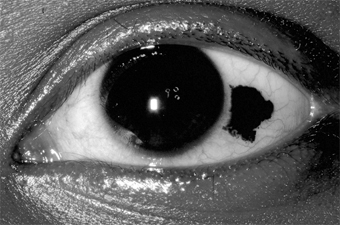

Chapter 5: Conjunctiva IV. CONJUNCTIVAL TUMORS PRIMARY BENIGN TUMORS OF THE CONJUNCTIVA Nevus (Figure 5-26) One-third of melanocytic nevi of the conjunctiva lack pigment. Over half have cystic epithelial inclusions that can be seen clinically. Histologically, conjunctival nevi are composed of nests or sheets of nevus cells. Conjunctival nevi, like other nevi, rarely become malignant. Many are excised because they are disfiguring. Pigmented conjunctival nevi must be distinguished from primary acquired melanosis of the conjunctiva. The latter occurs later in life (after the third decade), is usually unilateral, tends to wax and wane in degree of pigmentation, and, depending on the degree of cellular atypia, has a risk of becoming malignant ranging from nil to 90%. Papilloma Conjunctival papillomas occur in two forms: infectious papillomas, associated with a papovavirus, occurs in children and young adults, especially in the inferior fornix and near the medial canthus (Figure 5-27). The other type arises from a broad base, often near the limbus, in older adults and may be indistinguishable from conjunctival intraepithelial neoplasia. A biopsy may be required to establish the diagnosis. Granulomatous Inflammation Granulomatous inflammation occurs around foreign bodies, around extravasated sebaceous material in chalazia, and in association with diseases such as coccidioidomycosis and sarcoidosis. These inflammatory foci may form elevated plaques or nodules in the skin or the conjunctiva of the eyelids. Dermoid Tumor (Figure 5-28) This congenital tumor appears as a smooth, rounded, yellow elevated mass, frequently with hairs protruding. A dermoid tumor may remain quiescent, though it can increase in size. Removal is indicated only if cosmetic deformity is significant or if vision is impaired or threatened. Limbal dermoids and dermolipomas are most often isolated lesions, but occasionally they may be part of such syndromes as oculoauriculovertebral dysplasia (Goldenhar's syndrome). Dermolipoma Dermolipoma is a common congenital tumor that usually appears as a smoothly rounded growth in the upper temporal quadrant of the bulbar conjunctiva near the lateral canthus. Treatment is usually not indicated, but at least partial removal may be indicated if the growth is enlarging or is cosmetically disfiguring. Posterior dissection must be undertaken with extreme care (if at all) since this lesion is frequently continuous with orbital fat; orbital derangement may cause scarring and complications far more serious than the original lesion. Lymphoma & Lymphoid Hyperplasia These are conjunctival lesions that may appear in adults without evidence of systemic disease or associated with systemic lymphosarcoma or various blood dyscrasias. The clinical appearance of benign lymphoid hyperplasia and malignant lymphoma can be similar; therefore, biopsy is essential to establish a diagnosis. Since many of these lymphoid tumors may involve the orbit, an magnetic resonance imaging (MRI) or computed tomography (CT) scan may be required to determine the true extent of the tumor. Treatment of both benign and malignant lesions is best accomplished with radiotherapy. Angioma Conjunctival angiomas may occur as isolated, circumscribed capillary hemangiomas or as more diffuse vascular tumors, often associated with a more extensive lid or orbital capillary or cavernous hemangioma. Hemangiomas should be distinguished from telangiectases involving conjunctival capillaries. Telangiectatic conjunctival vessels may occur as isolated lesions or may be associated with systemic vascular hamartomas in Rendu-Osler-Weber disease or in ataxia-telangiectasia (Louis-Bar syndrome). Pyogenic granulomas are a variety of capillary hemangiomas. They frequently occur on the palpebral conjunctiva over chalazia or in an area of recent surgery. In Kaposi's sarcoma associated with AIDS, red-blue vascular nodules may first become apparent in the conjunctiva. They are associated with a herpesvirus. Radiotherapy is the most effective treatment. Bacillary angiomatosis is another proliferative vascular lesion that may appear similar to Kaposi's sarcoma. It is due to infection with gram-negative bacteria of the genus Bartonella-B henselae from cats in patients with AIDS and B quintana from body lice in low-income homeless individuals. These tumors respond to antibiotic therapy. PRIMARY MALIGNANT TUMORS OF THE BULBAR CONJUNCTIVA Carcinoma Carcinoma of the conjunctiva arises most frequently at the limbus in the area of the palpebral fissure and less often in nonexposed areas of the conjunctiva. Some of these tumors may resemble pterygia. Most have a gelatinous surface; sometimes, abnormal keratinization of the epithelium produces leukoplakia. Growth is slow, and deep invasion and metastases are extremely rare; therefore, complete excision is effective treatment. Recurrences are common if the lesion is incompletely excised; treatment consists of reexcision. The use of cryotherapy may help to prevent recurrences. Conjunctival dysplasia, also called atypical epithelial dysplasia, is a benign condition that occurs as an isolated lesion or sometimes over pterygia and pingueculae and can resemble carcinoma in situ clinically and even histologically. The term conjunctival intraepithelial neoplasia can be applied to all neoplastic lesions from dysplasia to carcinoma that are confined to the epithelium. Excisional biopsy will establish a diagnosis and result in cure of most of these lesions. Malignant Melanoma Malignant melanomas of the conjunctiva are rare. Most arise from areas of primary acquired melanosis; some arise from conjunctival nevi; a few apparently arise de novo from normal conjunctiva. Some are melanotic; others are heavily pigmented (Figure 5-29). Many tumors can be locally excised. More radical surgery (eg, exenteration of the orbit) does not usually improve the prognosis. The use of cryotherapy after excision of melanotic tumors may help to prevent recurrences. PREVIOUS | NEXT Page: 1 | 2 | 3 | 4 | 5 | 6 | 7 | 8 | 9 | 10 | 11 | 12 | 13 | 14 10.1036/1535-8860.ch5 |